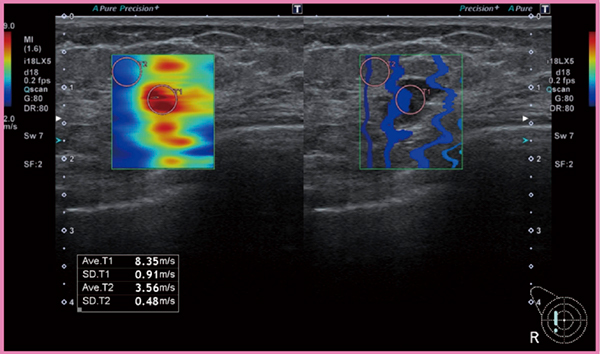

乳腺腫瘍の場合,悪性腫瘍は硬いことが多いため,硬さがわかれば診断の一助になりうる。硬さの情報を定量し画像化する技術として,SWEがある。この手法は,対象組織内を伝播する剪断波の速さを観測する手法であり,対象組織に固有の硬さの値を知ることができる。弾性体においては,剪断波伝播速度が大きいほど弾性率が高い,すなわち硬いということになる。

図3の画面左は,Shear waveの伝播速度のカラーマッピング表示である。本症例の乳腺腫瘍内の剪断波伝播速度は平均で8.35m/sであり,周辺組織に比べて速く,硬いことが映像化されている。画面右は,一定時間間隔で観察された剪断波の波面の位置を等高線状に表示したものである。腫瘍部のような硬いところでは剪断波が速く伝播するため線の間隔が広く,逆に腫瘍左の正常領域のような軟らかいところでは線の間隔が狭くなる。Shear waveの伝播速度は,対象組織に加わる圧力で変化する性質がある。乳腺にShear waveを適用する場合は,プローブの接触圧力に留意する必要がある。

図3 乳腺のSWE像

(画像提供:名古屋医療センター・森田孝子先生)